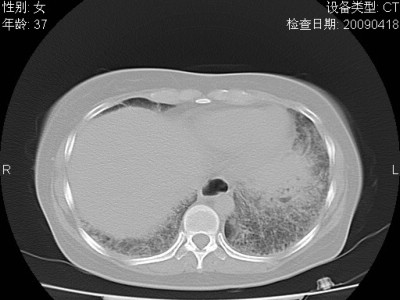

以下是引用随光逐影在2009-4-20 8:03:00的发言:[br]两肺间质性病变(间质性肺炎?特发性肺间质纤维化?)。

以下是引用51736011在2009-4-21 16:24:00的发言:[br]两肺间质性病变(间质性肺炎?特发性肺间质纤维化?)。